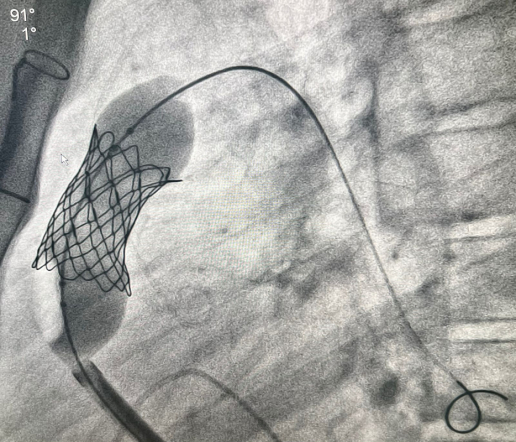

У пациента из Луганской Народной Республики просвет ранее имплантированного кондуита составлял 1,5 сантиметра, поэтому рентгенхирурги на первом этапе расширили его методом баллонной дилатации. При этом был риск разрыва сосуда, поэтому, чтобы избежать возможных осложнений, медики сначала имплантировали стентграфт – металлический каркас, покрытый герметичным полимером. Просвет кондуита удалось расширить до необходимого диаметра. Затем через бедренную вену хирурги доставили к сердцу искусственный биологический клапан лёгочной артерии Myval индийского производства.

Сложную операцию провела команда врачей Педиатрического университета - рентгенэндоваскулярные хирурги Михаил Комиссаров, Владимир Приворотский и Иван Алешин. Неоценимую помощь медикам СПбГПМУ оказал заведующий отделением рентгенэндоваскулярных методов диагностики и лечения  Городской многопрофильной больницы №2 Евгений Шлойдо.